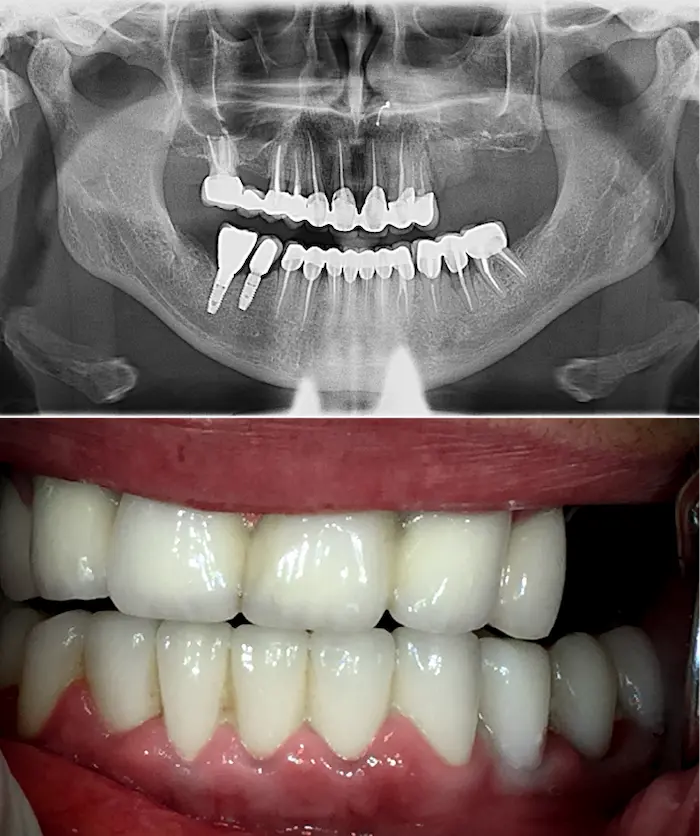

Una soluzione esiste: con gli impianti dentali zigomatici e gli impianti subperiostali (o impianti sottoperiostei) puoi ottenere denti fissi anche in assenza totale di osso mascellare.

Gli impianti dentali zigomatici fissi sono impianti in titanio lunghi 3 – 6 cm che si ancorano all’osso zigomatico, molto più denso e stabile dell’osso mascellare. In base alle necessità il chirurgo definirà se utilizzare un impianto Zygoma Quad (due impianti zigomatici per lato), Zygoma Hybrid oppure Zygoma Laterale.

Gli impianti sottoperiostei (o impianti subperiostali) vengono creati su misura, in titanio puro T4 completamente biocompatibile, e applicati sulla superficie dell’osso residuo.

Sono progettati digitalmente per adattarsi alla tua anatomia in presenza di atrofia ossea severa.

Applicazione della protesi definitiva

Dopo 4 – 6 mesi, quando l’impianto ha concluso il processo di integrazione ossea, si procede con l’applicazione della protesi fissa definitiva.